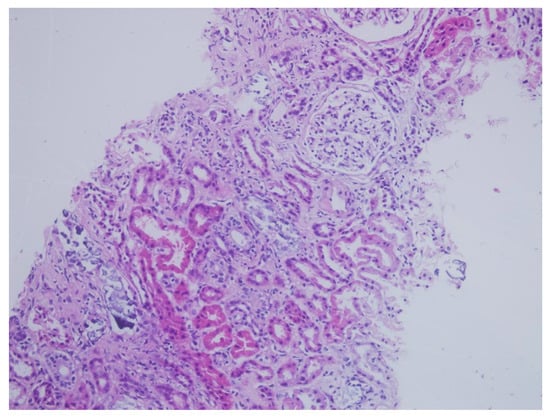

| Interstitial inflammation * | Mild; Eo, Mn | Mild; Lym | Mild; Mn | Mild; Lym | Mild; Lym | Mild; Lym | Mild; Lym | Mild; Mn | Mild; Lym |

| Tubular atrophy * | − | Moderate | Mild | − | − | − | Mild | Moderate | − |

| Tubulointerstitial deposition | + | + | + | + | + | + | + | + | + |

| Interstitial fibrosis * | − | − | Mild | − | − | − | − | Mild | − |

| Tubular necrosis | − | − | + | − | − | − | − | − | − |